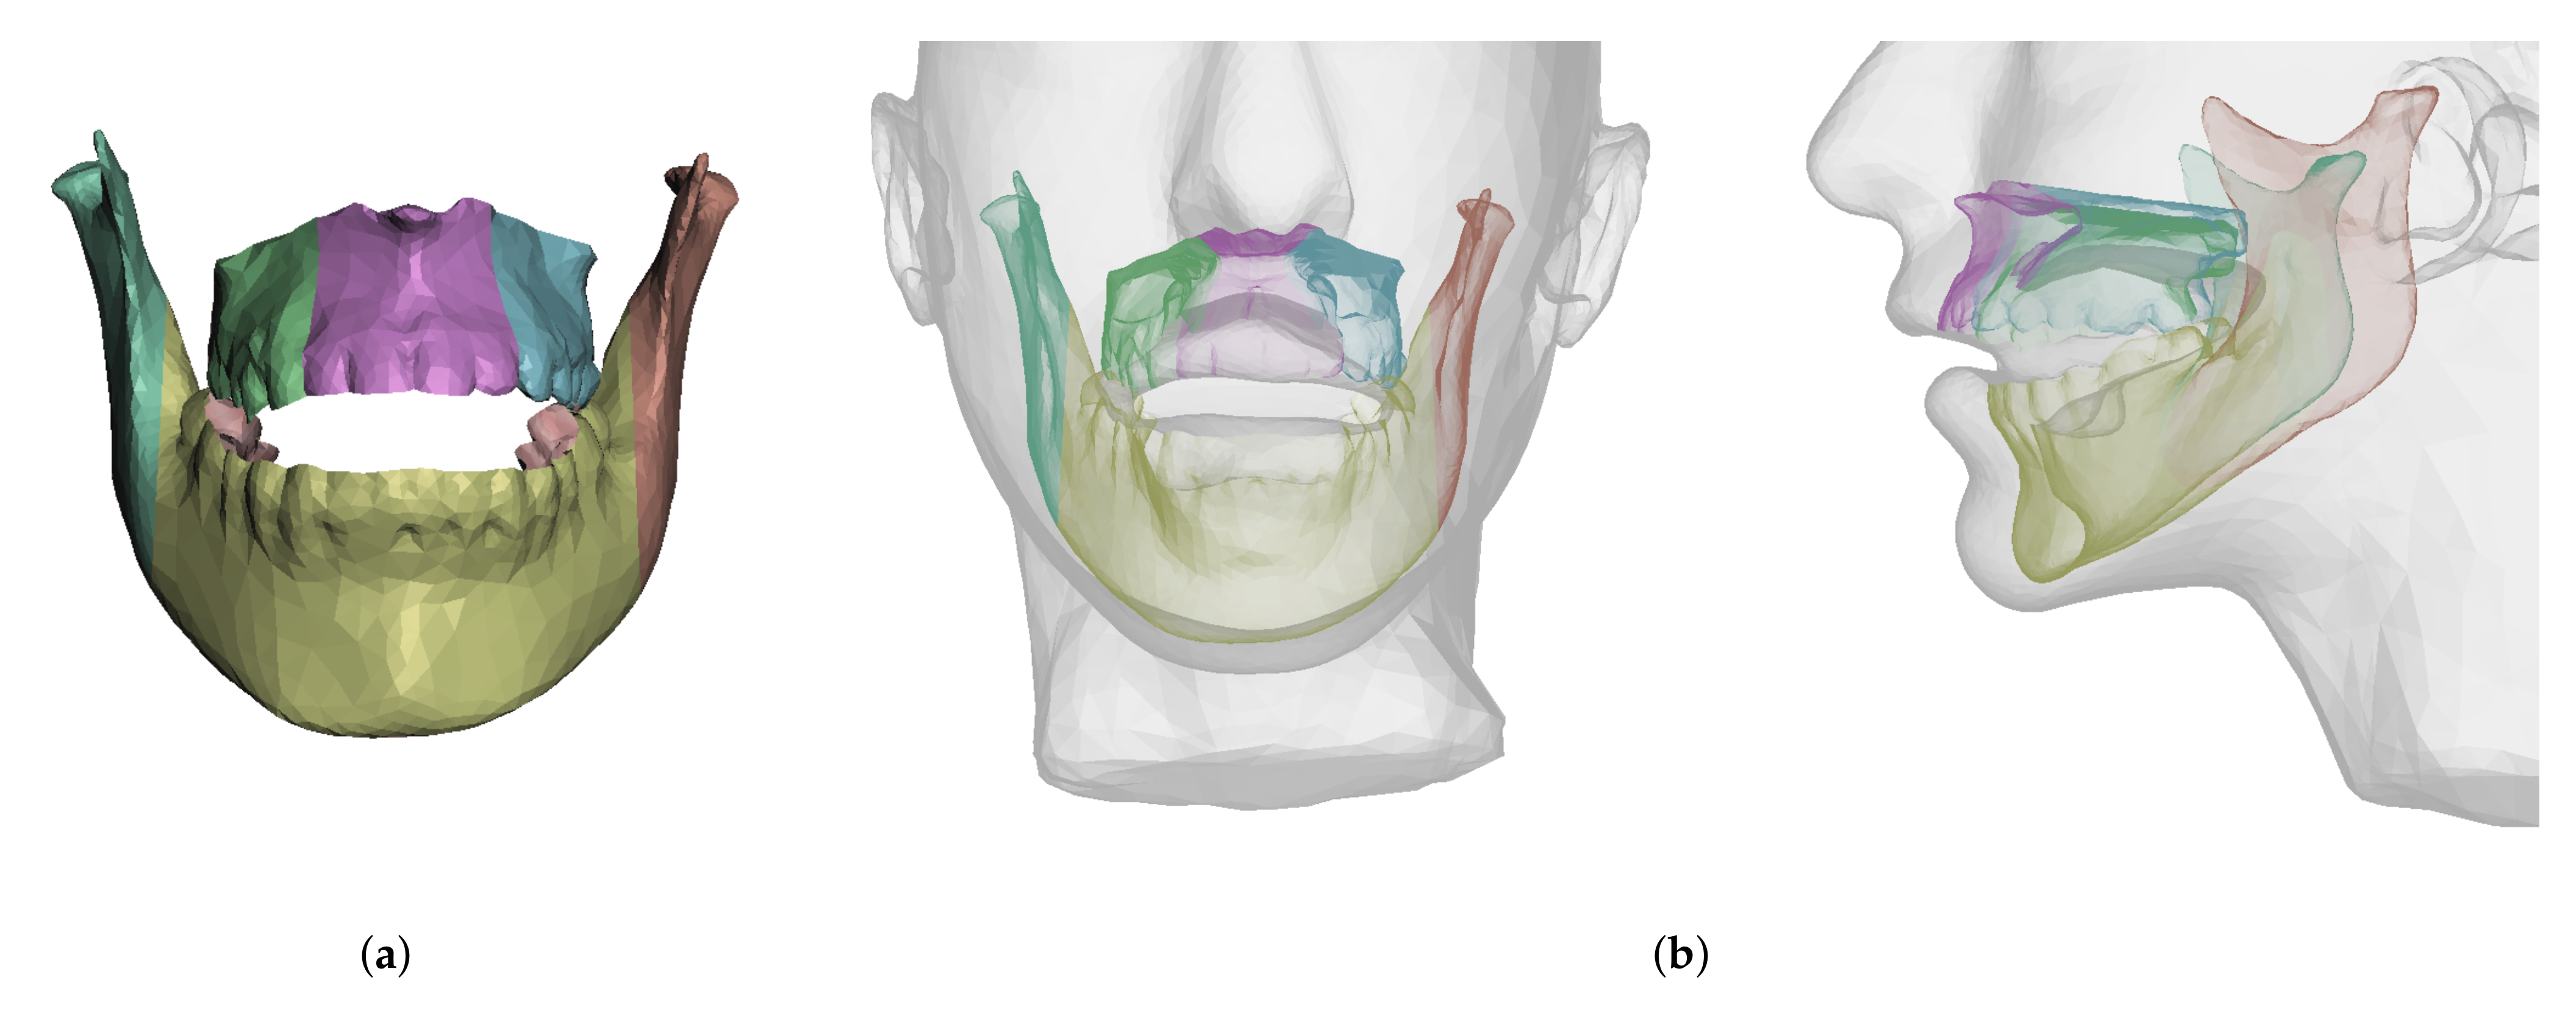

2.5.1. Bones

2.5.2. Soft Tissue

- In maxillary procedures, the maxilla is separated from the skull through a Lefort osteotomy, classified based on its anatomical level. In this cohort, the distribution of cases is: 8 Lefort I cases and 1 Lefort II case; one patient did not undergo maxillary surgery. Moreover, after a Lefort I osteotomy, the maxilla may be segmented (typically into three fragments) in order to expand the upper arch. Maxilla segmentation was applied to 6 patients in this cohort.

- In mandibular procedures, the mandible may be sagittally split on both rami (bilateral sagittal split osteotomy, BSSO) or only one ramus (unilateral sagittal split osteotomy, USSO). In this cohort, the distribution of cases is: 7 BSSO cases, 1 USSO case; two patients did not undergo mandibular surgery. Additionally, a chin osteotomy or genioplasty may be also performed. Genioplasty was applied to 1 patient in this cohort.